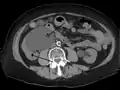

Hydronephrosis due to a kidney stone at the ureteral vesicular junction seen on CT scan